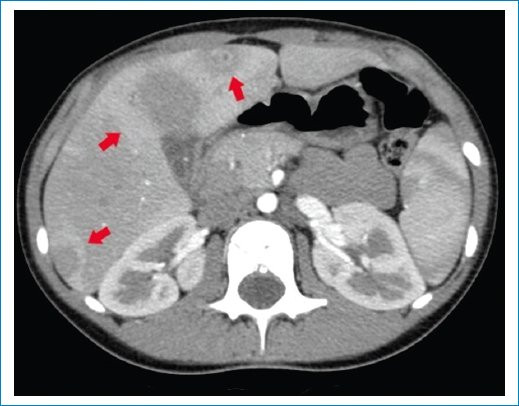

Se trata de una paciente de sexo femenino de 9 años, previamente sana, quien consultó al servicio de guardia pediátrica de nuestra institución por presentar síndrome febril prolongado de 12 días de evolución, sin otro síntoma asociado. A su ingreso, el examen físico reveló buen aspecto general. Se realizó una ecografía abdominal donde se evidenciaron lesiones redondeadas, hipoecoicas, de bordes regulares, que comprometían el parénquima hepático y esplénico (Figs. 1 y 2), las cuales fueron interpretadas como abscesos. Se complementó su estudio con tomografía computada (TC) de abdomen y pelvis con contraste endovenoso, siendo el hallazgo principal la presencia de múltiples imágenes hipodensas con morfología en racimos y realce en anillo tras la administración del contraste endovenoso, distribuidas en el parénquima hepático y esplénico, destacándose la mayor de 29 mm en segmento V hepático (Figs. 3 y 4). Debido a los hallazgos por imágenes y el estado clínico de la paciente, el primer diagnóstico que se planteó fue el de EAG. Se consideraron las lesiones hipodensas múltiples del hígado y bazo como una manifestación importante de enfermedad diseminada o atípica3,5,6. La madre confirmó un gato como mascota, lo cual estaba a favor de nuestra impresión diagnóstica.

Para realizar el diagnóstico de EAG se utilizan pruebas serológicas que detectan la presencia de anticuerpos contra B. henselae4,8. A nuestra paciente se le realizaron pruebas de anticuerpos B. henselae IGG e IGM cuyo resultado fue positivo (1/1.280). Los estudios de imágenes poco aportan ante cuadros de EAG típico, podemos encontrar en la evaluación ecográfica ganglios linfáticos aumentados de tamaño con pérdida de su ecoestructura habitual, generalmente con necrosis central y asociados a edema circundante. Sin embargo, en pacientes con enfermedad atípica o diseminada se han asociado hallazgos característicos que pueden ser útiles para establecer el diagnóstico como la formación de múltiples granulomas hepáticos y esplénicos, con o sin hepatoesplenomegalia, identificados mediante ecografía y TC3. Estos granulomas se identifican inicialmente como lesiones hipoecoicas en ecografía, y en algunos casos presencia de calcificaciones en las fases tardías. En TC presentan características similares a cualquier absceso, hipodensos, redondeados o con morfología en racimos y tras la administración del contraste pueden permanecer hipodensos o mostrar un realce periférico característico. La multiplicidad y el compromiso de varios órganos se relacionan más con infecciones bacterianas, a diferencia de las de origen parasitario, lo cual nos orienta a un mejor diagnóstico.